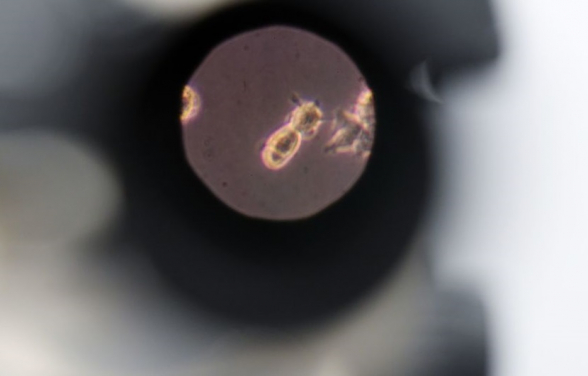

Ֆիլիպիններում կորոնավիրուսի` մուտացիայի ենթարկված մանրէահիմք է հայտնաբերվել։ Տեղեկությունը հայտնում է The Straits Times-ը։

G614 նոր մանրէահիմքը հայտնաբերել են Կեսոն Սիթիի հիվանդների մոտ։ Բժիշկների տվյալներով՝ մուտացիան ի հայտ է եկել դեռ հունիսին։

Միաժամանակ բժիշկները հայտնում են` դեռևս հաստատված չէ, որ G614 վիրուսի կրողներն ավելի վարակիչ են, քան նրանք, ում մոտ կորոնավիրուսի սկզբնական մանրէահիմք է հայտնաբերվել:

Նրանց խոսքով՝ վիրուսի մուտացիան ամենայն հավանականությամբ չի ազդի կլինիկական ցուցանիշների վրա։

Բժիշկները հույս ունեն, որ վարակի նոր մանրէահիմքը չի ավելացնի մահացության թիվը։